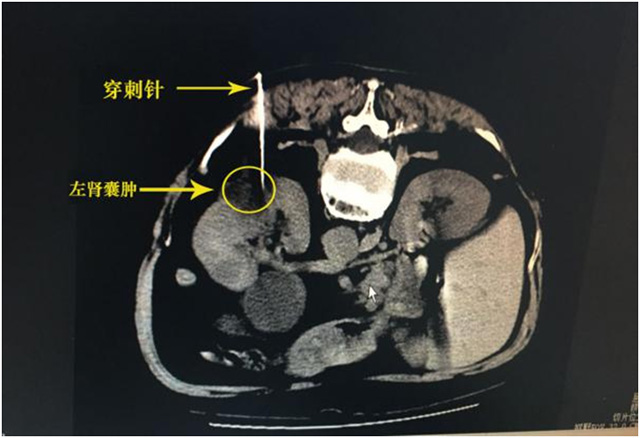

5月29日,我院放射科成功為一患者行全縣首例CT引導(dǎo)下左腎囊腫經(jīng)皮穿刺固化術(shù)。

5月22日,患者因左腎囊腫入院就診,患者近10年來(lái)復(fù)查彩超左腎囊腫逐漸增大,近期彩超提示“左腎多發(fā)囊腫,最大約5.8*5.0cm”。入院時(shí)偶感左側(cè)腰部脹痛不適,既往慢支炎,高血壓病。入院后完善相關(guān)輔查,發(fā)現(xiàn)患者有心臟病,且肺部情況差,外科手術(shù)風(fēng)險(xiǎn)大,而CT引導(dǎo)下左腎囊腫經(jīng)皮穿刺固化術(shù)是一種創(chuàng)傷小,并發(fā)癥小,費(fèi)用低,療效好的微創(chuàng)治療方法,征得家屬同意后,由放射科李毓橋副主任醫(yī)師在CT引導(dǎo)下為患者進(jìn)行左腎囊腫經(jīng)皮穿刺固化術(shù),術(shù)中先后對(duì)其多個(gè)囊腫進(jìn)行了處理,手術(shù)順利,術(shù)后患者情況良好,病情穩(wěn)定,返病房進(jìn)行后續(xù)治療。

CT是斷層圖像,可清楚顯示病變大小、形狀、位置、與周圍組織關(guān)系,能精準(zhǔn)確定穿刺針進(jìn)針部位、深度、角度等,CT引導(dǎo)下左腎囊腫經(jīng)皮穿刺固化術(shù)的開(kāi)展將減輕患者痛苦及經(jīng)濟(jì)負(fù)擔(dān),讓患者足不出縣便能享受三甲醫(yī)院的醫(yī)療服務(wù)。

CT影像下的介入治療